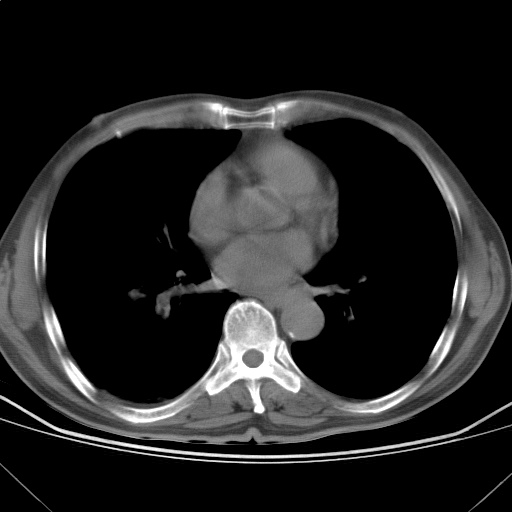

以下是引用随光逐影在2009-5-1 13:53:00的发言:[br]考虑为:1)两肺血行播散型肺结核;2)右肺下叶炎症感染。3)右侧胸膜增厚。